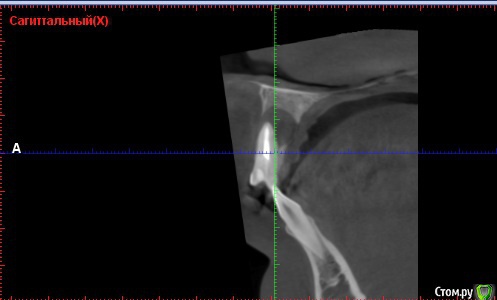

Andre_ Опубликовано 22 октября, 2015 Поделиться Опубликовано 22 октября, 2015 Верхней челюсти кисты, если быть точнее. Терапевт пробовал перепроходить - цемент. Пациент - молодой парень, крайне хочется, чтобы ушёл с зубами, хотя бы временными. Какой бы вы план действий преложили? Ссылка на комментарий

DmitrySH Опубликовано 22 октября, 2015 Поделиться Опубликовано 22 октября, 2015 Есть смысл пробовать ещё? Да вы еще и не попробовали толком. Передайте пациента эндодонтисту со скопом и будет всем счастье.Под микроскопом цемент расломбировать в прямом канале.. вообще никаких проблем. Поводов для хирургии на данный момент нет. 7 Ссылка на комментарий

Дмитрий Никитюк Опубликовано 23 октября, 2015 Поделиться Опубликовано 23 октября, 2015 Забудьте про диагноз "киста", это моветон. Подобные диагнозы можно ставить только после гистологии. Есть диагноз "апикальный периодонтит". Соответственно и подход к лечению при таком диагнозе не предполагает на первом этапе никакой хирургии, только ретрит. Затем динамическое наблюдение и принятие решения по хирургическому лечению, в случае неэффективности консервативного. 5 Ссылка на комментарий